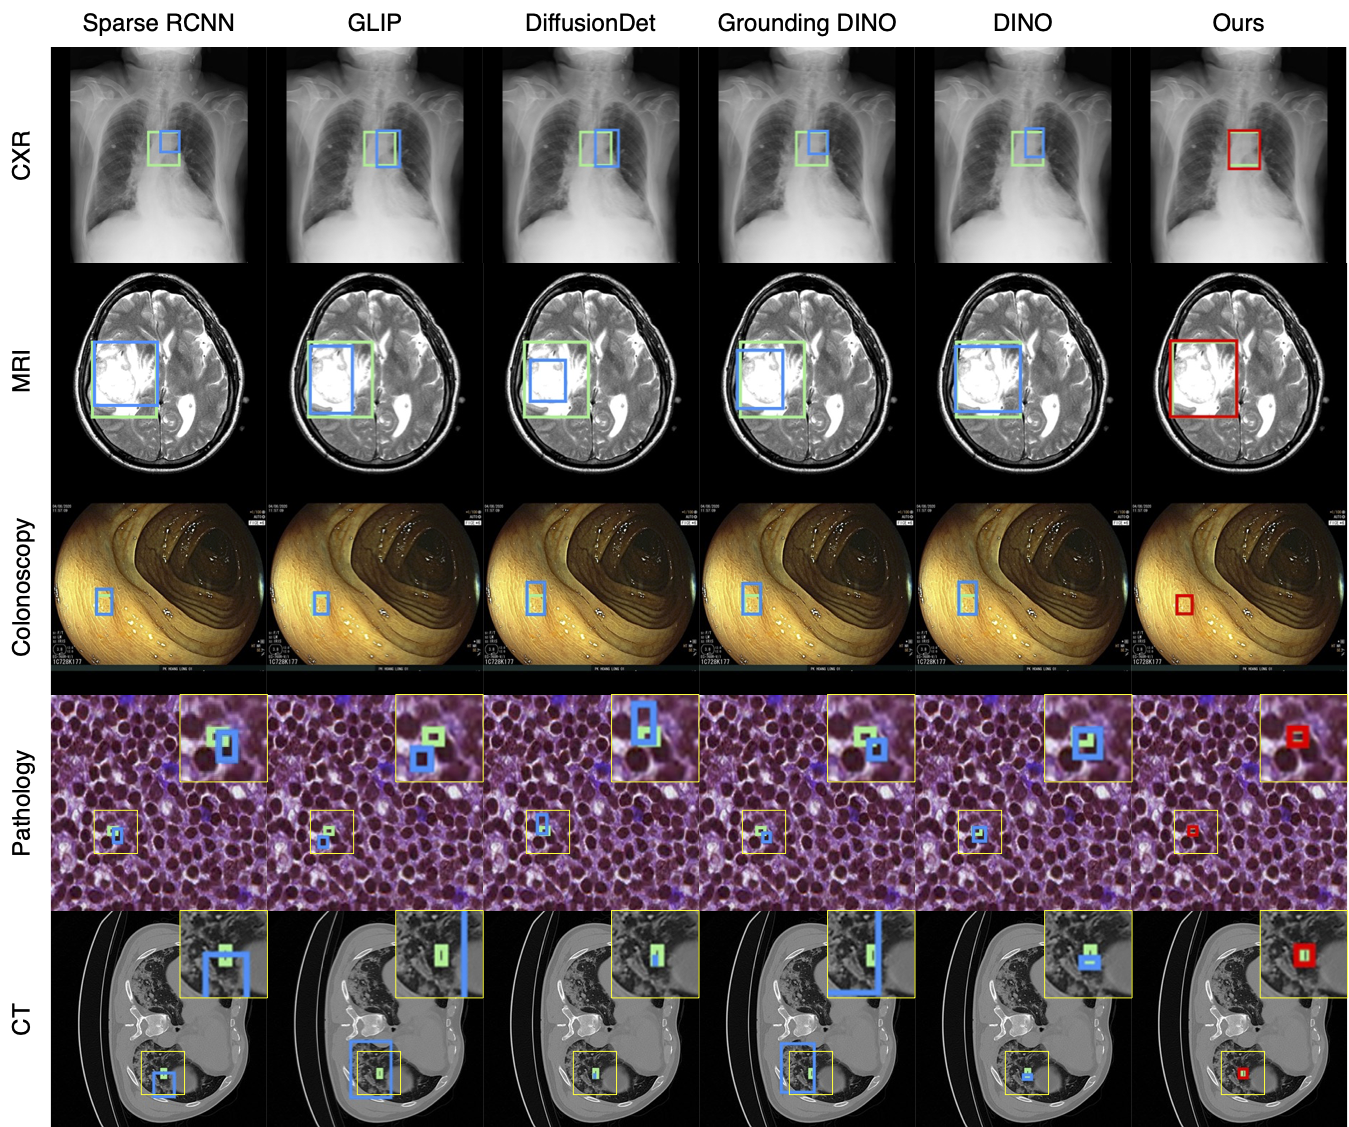

Comparison with other detectors

Comparison of text/modality integration in DETR-style detectors.

(a) DINO (baseline): image-only encoder–decoder with query selection.

(b) Grounding DINO: language-guided query selection and cross-attention in the decoder (object queries attend to a sequence of text tokens).

(c) Ours (DINO+MoCA): append compact modality tokens to the object queries and fuse by self-attention in the decoder; the tokens act as semantic anchors that refine queries in a modality-aware way with minimal overhead.

Qualitative comparison results

Qualitative Comparison. Comparison results between various state-of-the-art detection methods and the proposed method is shown above. Our method effectively leverages modality context to significantly enhance anomaly localization (red), compared to baseline results (blue). Ground truth bounding boxes are green. For cases where the bounding boxes are small, insets show an enlarged view of the highlighted yellow region.